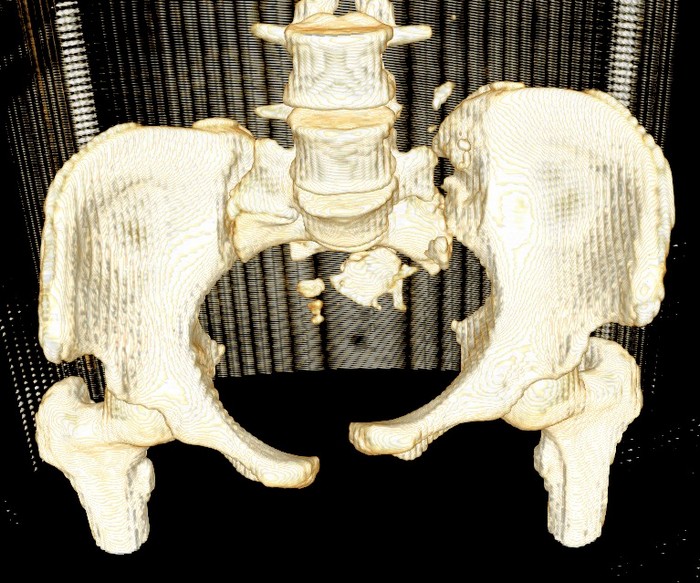

Девочка 14 лет. Кататравма (падение с высоты 4-5 этажа). Вертикально нестабильный перелом таза со смещением, разрывом лонного и левого подвздошно-крестцового сочленения, перелом крестца, открытый перелом костей голени. Ребёнок оперирован на 10-е сутки после травмы - выполнили максимально возможную репозицию на ортопедическом столе, синтез лонного сочленения реконструктивной пластиной (из имеющихся пластин - на 7 дыр - самая длинная, получилось только по 2 шурупа с каждой стороны, поэтому пришлось подстраховаться проволокой), АВФ. Задний комплекс не фиксировали ввиду отсутствия канюлированных (да и неканюлированных)шурупов должной длинны.В настоящий момент перед нами стоит вопросов:1. Обязательно ли фиксировать подвздошно-крестцовое сочленение, либо фиксации АВФ будет достаточно? Аппарат стоит достаточно стабильно, девочка при перемещениях в пределах постельного режима болевых ощущений не испытывает.2. Что делать с отломком крестца, который довольно значительно смещён кпереди? В настоящий момент никаких проблем с дефекацией у больной нет, хотя, глядя на КТ, создаётся впечатление, что отломок прямо-таки лежит на прямой кишке. Репонировать-фиксировать? Просто удалить? Вообще не трогать? Не создаст ли он в дальнейшем проблем во время родов?Хотелось бы знать мнение уважаемых коллег.Заранее спасибо.

Здравствуйте, Сергей! Нестабильный перелом типа С подлежит обязательной задней фиксации или илиосакральными винтами, или пластиной, или стяжкой (кто что лучше умеет и чем оснащен). Возможен циркулярный АВФ (Уральский НИИТО). В Вашем случае, при невозможности восстановления заднего комплекса,- постельный режим до 2-х месяцев. Учитывая недостаточную репозицию в крестцово-подвздошном сочленении в будущем девочка обречена на хронический болевой синдром. Может быть стоило выполнить репозицию отломков в аппарате, а вторым этапом делать погружной остеосинтез. Костный фрагмент, думаю, можно оставить. После такой травмы речь будет идти о кесаревом сечении, а не о родах естественным путем.

Это не частый случай в детской практике. Вы очень хорошо сопоставили и фиксировали переднее полукольцо. Крестцово-подвздошное осталось в приличном смещении. Прекрасно - что нет неврологической клиники. Сейчас больная лежит. Поэтому всё хорошо. Учитывая соотношение крестец-подвздошная кость - кажется, что первые же проблемы возникнут при попытке поставить больного на ноги. Разорваны важнейшие стабилизирующие и воспринимающие нагрузку связки в системе позвоночник-крестец-таз. В таком положении фрагменов их адекватное восстановление и последующее функционирование , как мне кажется, не возможно. В возрасте 14 лет это взаимоотношение критично. Я имею в виду отсутствие репозиции. появление нестабильности, по-видимому, будет неизбежно. Это моё маленькое скромное мнение. Всё же надо было начинать сзади. Именно с репозиции. Фиксацию, ИМХО, можно было бы на безрыбье временно сделать и спицами (например-с резьбой) интраоперационно. В идеале - с навигатором, чтобы не задеть крестцовый канал, или с пальцем, контролирующим положение отломков над гребнем подвздоной кости и "навигирующим" проведение спицы. Сейчас Вам это сделать помешает LCP, жёстко фиксирующая переднее полукольцо и смещенное положение отломков. АВФ не "прижмёт" подвздошную кость к крестцу, и не выполнит репозицию. Возраст больной, мне кажется, не простит в дальнейшем погрешность в положении костей и, чем дальше, тем труднее будет исправлять . Это только мнение и ничего личного.Прямая кишка здесь в меньшей степени заинтересована - это вовсем не главное. Вероятные роды в насоящей тактике лечения совсем не играют решающей роли. Всё же - как неврология?

Извините! Нет срезов, а задний комплекс справа интактен?